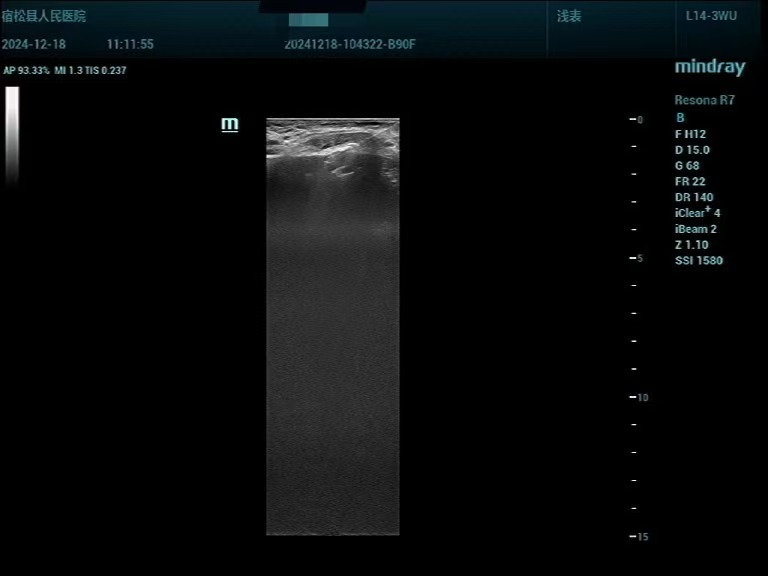

▲根据超声造影结果,超声引导下对活性病变组织取材